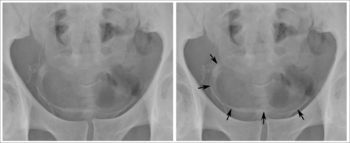

Genitourinary disease

The worms of S. haematobium migrate to the veins around the bladder and ureters.[21] This can lead to blood in the urine 10 to 12 weeks after infection.[14][17] Over time, fibrosis can lead to obstruction of the urinary tract, hydronephrosis and kidney failure.[14][17] Bladder cancer diagnosis and mortality are generally elevated in affected areas, and efforts to control schistosomiasis in Egypt have led to decreases in the bladder cancer rate.[17][23] The risk of bladder cancer appears to be especially high in male smokers, perhaps due to chronic irritation of the bladder lining allowing it to be exposed to carcinogens from smoking.[17][19]